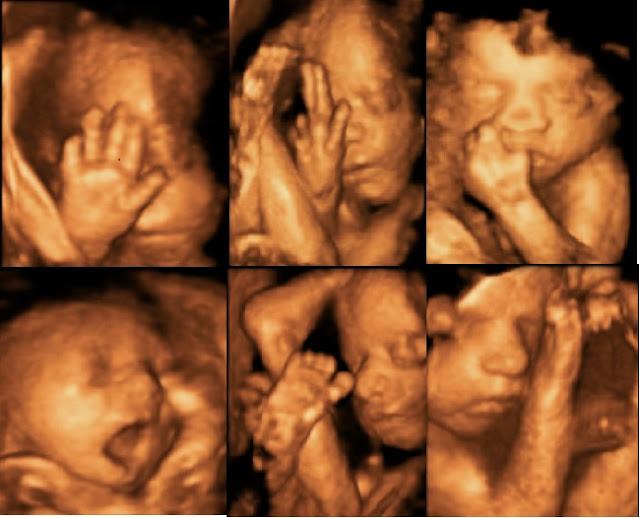

Recuerdo con especial cariño los tres momentos en los que me hicieron las ecografías y tuve esa primera visión de lo que sería mi bebé. Esos momentos, las ecografías trimestrales, son de gran importancia tanto para las madres como para los futuros bebés. En ellas buscamos que nos confirmen que nuestro bebe goza de buena salud, pero también buscamos tener esas primeras imágenes para sincronizarlas con todo lo que estamos sintiendo.Con los equipos de antes, realmente ver, se veía poco. Con las indicaciones del médico y la mucha imaginación que le echábamos, lográbamos discernir si era niña o niño y ver al bebé muy difusamente. Pero esos momentos eran realmente especiales. Hoy en día esta tecnología ha avanzado mucho y tenemos que hacer obligada la diferencia entre las clásicas, y necesarias, ecografías de diagnóstico y las ecografías emocionales. Estas últimas con la tecnología 3D y 4D que se hacen más pensando en el corazón de la madre que en los latidos del pequeño, y a estas son a las que quiero dedicar el presente post. Las ecografías emocionales ¿Necesarias? La pregunta a la necesidad de las ecografías emocionales tiene una respuesta ambigua y depende en todo caso de la situación de la madre y su predisposición. Hay que tener en cuenta que esta técnica no está cubierta por la seguridad social y debemos desembolsar nuestro dinero. Sin embargo, debido al auge del sector, la oferta de este servicio se ha incrementado, haciéndose realmente competitiva y asequible. Si visitas la blogosfera, puedes observar que cada vez más madres apuestan por esta técnica en busca de un recuerdo inolvidable. Los comentarios de muchas madres reflejan que se arrepienten de no haber disfrutado uno de los momentos más especiales en el embarazo. Y es que aunque la situación ahora mismo no es la idónea, hay sensaciones que no las paga el dinero. Estas ecografías tienen en su momento idóneo entre la semana 25 y 28 para ver todos los rasgos del bebé, aunque se pueden hacer desde la semana 12 hasta la semana 30 aproximadamente. Tienen un carácter muy humano. Quedan atrás los trasiegos médicos y técnicos para dejar paso a un ambiente en el que los padres y la familia ganan protagonismo. Eso sí, sin quitar el papel estelar de la pequeña personita que todos observan con absoluta devoción. Ecografías domésticas Ya hemos comentado anteriormente, que muchos padres y madres cada vez asisten a centros especializados en busca de esta imagen única y especial fuera de la diagnosis. Pero existen otras opciones que cada vez van ganando más adeptos gracias en parte al valor añadido que proporcionan. La posibilidad de realizar una ecografía en casa. Ya se sabe el dicho de ”como en casa en ningún sitio”. En este caso tiene todo el significado del mundo. Tener la posibilidad de estar en el hogar con la familia y amigos o bien en la intimidad, a la espera de ver al bebé moverse en su pequeño universo. Cualquier movimiento por su parte será capaz de dibujar la sonrisa más duradera y recordada de la familia.Si cuando yo estuve embarazada hubiese tenido esa oportunidad, sin duda hubiese querido ver a mi bebé por primera vez en casa.Y tú ¿Qué opinas de las ecografías emocionales? ¿Te hubiese gustado hacerte una? ¿Te lo estás planteando?¡Deja tus comentarios sobre el tema, estaré encantada de verlos! ¡Un abrazo y hasta pronto!

Imagen de Nadó4D